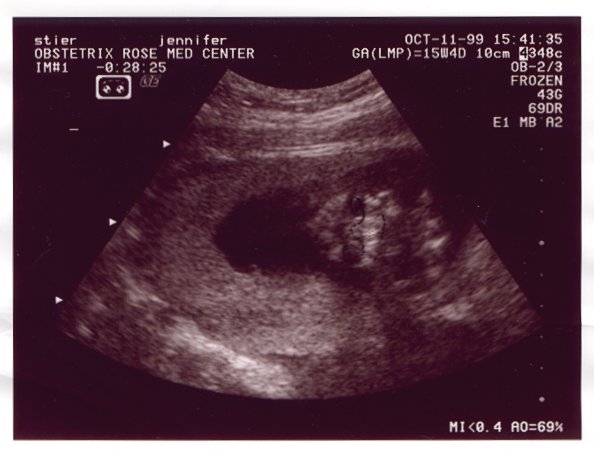

Ultrasound Picture No. 3